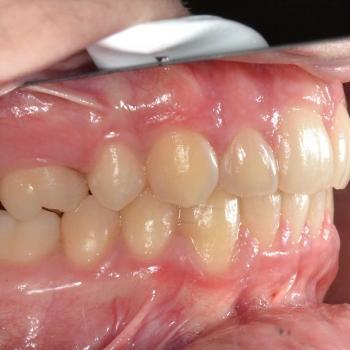

Benjamin és édesanyja az alsó és felső fogíven tapasztalható torlódás miatt kerestek fel, ám az első vizsgálat alkalmával fény derült a jobb felső 5-ös fog csírahiányára, mélyharapásra és féloldali Angle II-es harapási eltérésre is.

A kezelést hagyományos fém fogszabályozóval kezdtük el, melyet bite turbo harapásemelővel egészítettünk ki. A kezelés későbbi fázisában a szimmetria megteremtése érdekében eltávolításra kerül a bal felső maradó 4-es fog is és ezzel párhuzamosan különböző intermaxilláris gumihúzásokat vezettünk be.